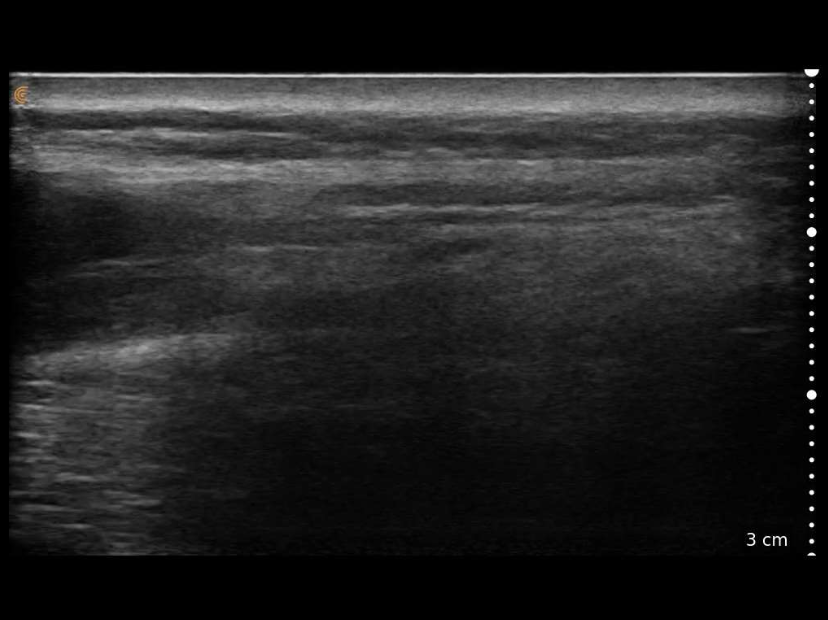

Original Ultrasound Scan

3 cm scale